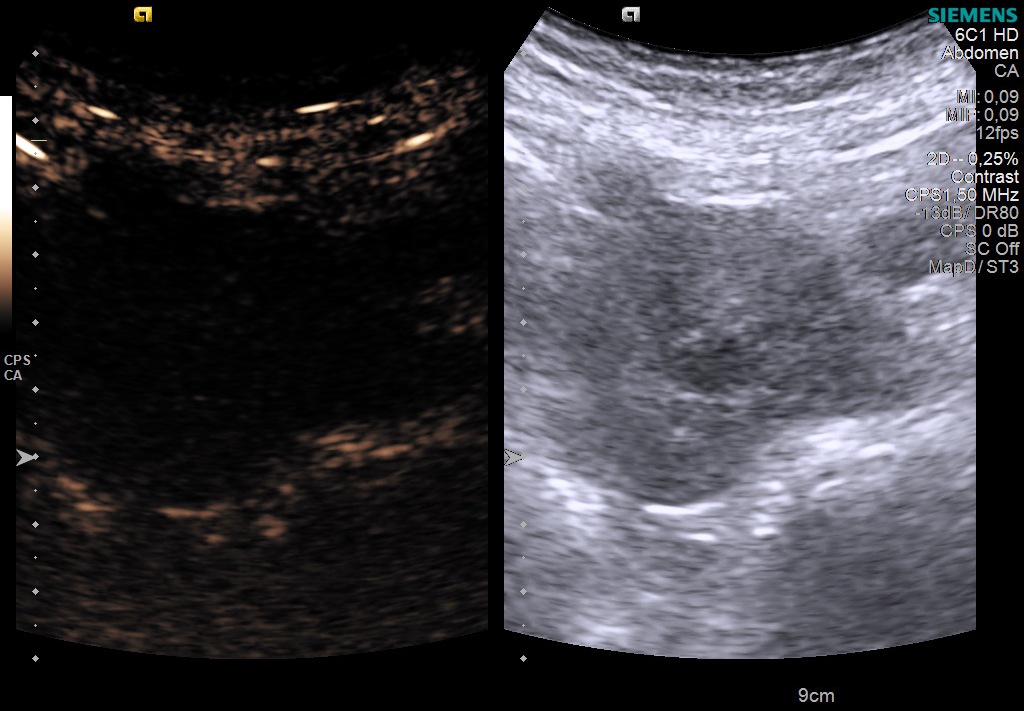

The following US aspect was found in a 70 yo male with weight loss for the past 6 months, upper abdominal pain, facial flushing and diarrhea. What is your diagnosis?

Case courtesy of Prof Adrian Saftoiu